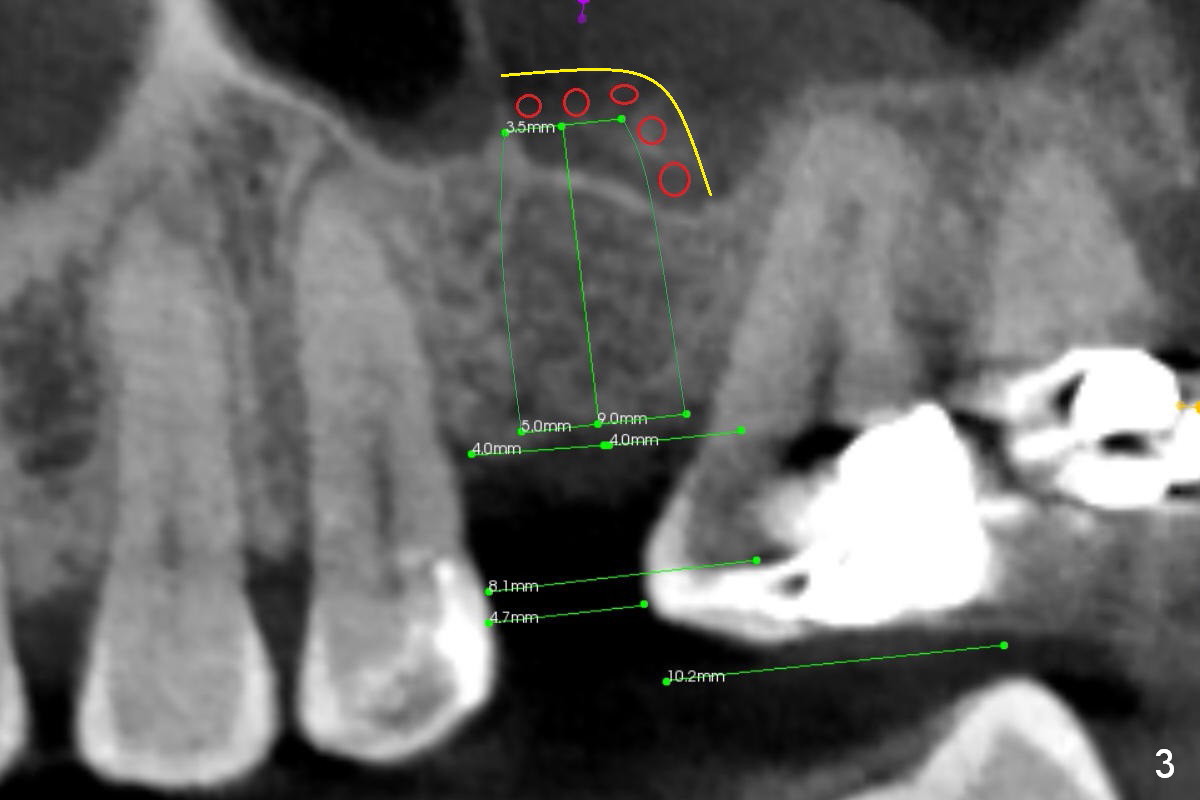

CT shows a residual root in the left maxillary sinus. In order not to re-infect the sinus, an implant at the site of #14 should not enter the sinus (Fig.2) or enters the sinus with bone graft (Fig.3,4 red circles) and more importantly PRF membrane (yellow).